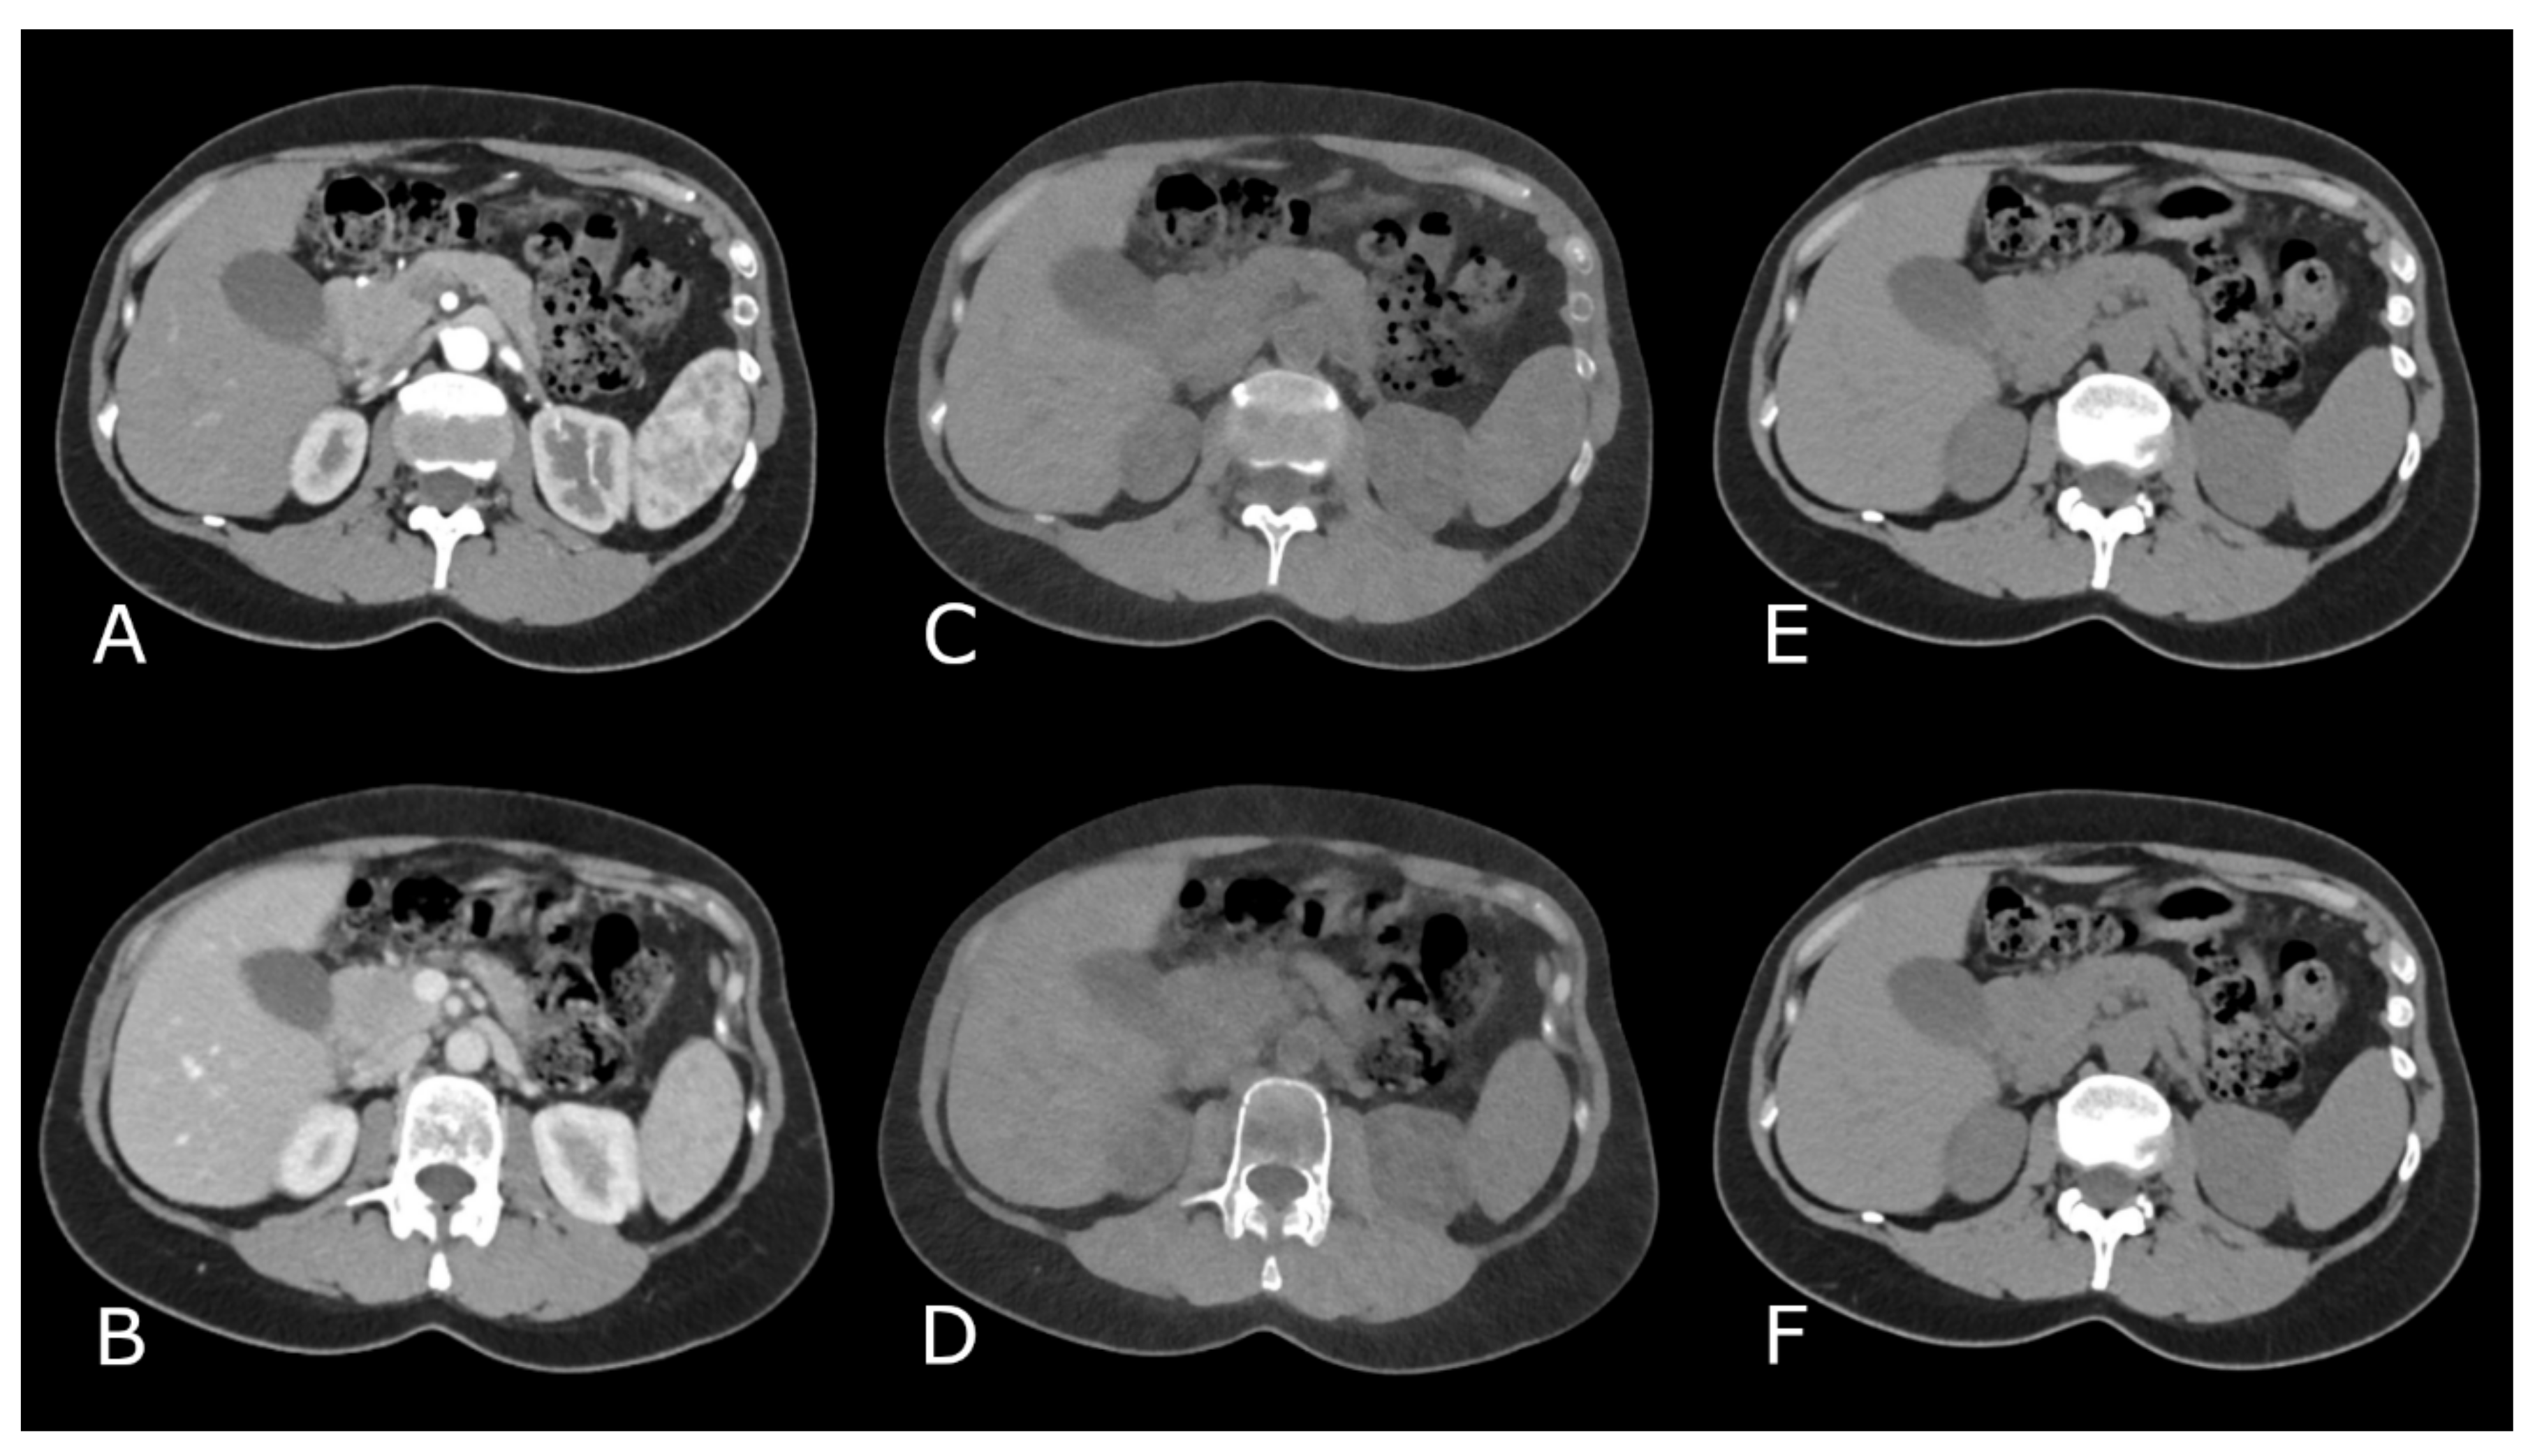

3.1.1. TNC versus VNCv

3.1.2. TNC versus VNCa

3.1.3. VNCv versus VNCa